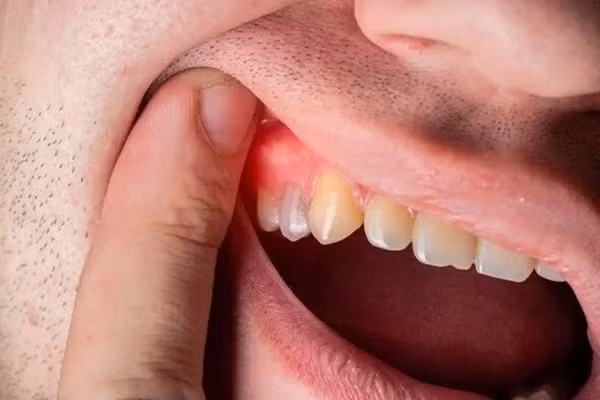

Bệnh nha chu thường do nhiễm trùng, viêm nướu và xương răng. Theo Trung tâm Kiểm soát và Phòng ngừa Dịch bệnh Hoa Kỳ, ở giai đoạn bệnh viêm nha chu nghiêm trọng, nướu có thể bị kéo ra khỏi răng, tiêu xương răng khiến răng bị lỏng lẻo hoặc thậm chí bị rụng sớm.

Thông thường, các biểu hiện của bệnh nha chu giống như bệnh sâu răng, bao gồm nướu bị đỏ và sưng. Tuy nhiên, nếu bạn thấy phần dưới cùng của răng có 3 màu sắc này tích tụ thì cũng hãy nghĩ đến khả năng là dấu hiệu cảnh báo viêm nha chu.

Chia sẻ trên trang Express Daily, bác sĩ Mani Bhardwaj, Giám đốc lâm sàng và nha sĩ chính tại Tập đoàn Nha khoa Smile Studios, cho biết: "Trong bệnh nha chu tiến triển, bạn có thể thấy nhận thấy ở xung quanh cổ răng gần đường nướu có tích tụ các cao răng màu xanh lá cây, nâu, vàng sẫm". "Kèm theo đó là các triệu chứng khác như hơi thở hôi, nướu có thể có dấu hiệu co hoặc tụt lại và răng có thể trở nên lỏng lẻo, bị nghiêng do mất nền xương", BS Mani nói thêm.

Ngoài dấu hiệu rõ ràng cảnh báo bệnh nướu răng như trên, BS Mani cũng khuyến cáo mọi người cần cảnh giác với một số biểu hiện khác như:

- Nướu răng mềm hoặc chảy máu;

- Nhai đau;

- Răng lỏng lẻo;

- Răng nhạy cảm;

- Nướu bị tụt khỏi răng;

- Bất kỳ thay đổi nào trong khớp cắn.